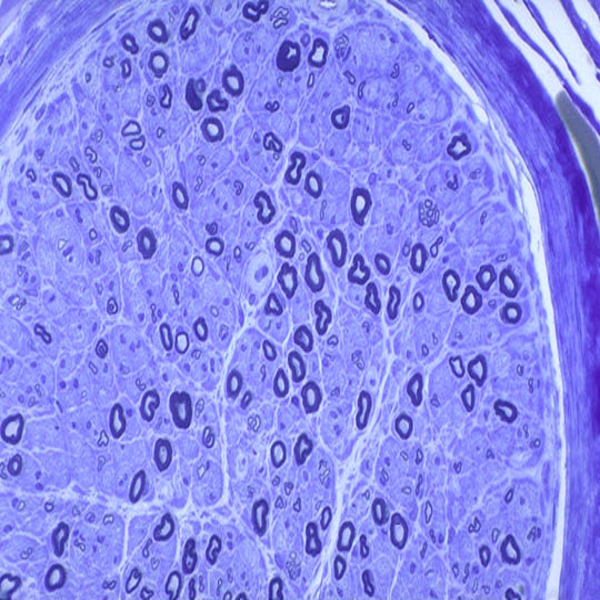

- General and specialized tissue and cell staining

- Prepare educational slides for students from all available tissues

Histological methods includes sample processing in the pathology laboratory, preparation of the slide and its examination under a microscope, sample fixation, molding, microtome cutting, staining and assembly of the slides.